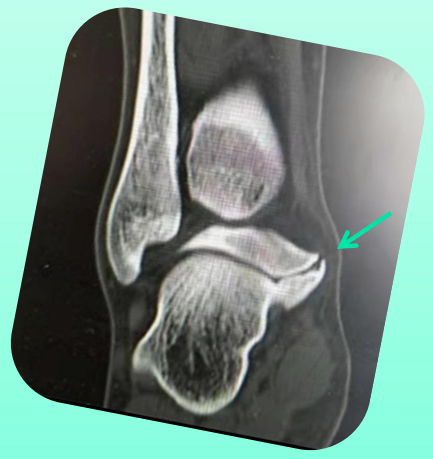

CT是诊断跟距骨桥的金标准

• CT可发现关节周围退变范围和骨性桥接涉及关节面的范围。

• CT可鉴别骨性骨桥和非骨性骨桥。

• CT难以显示纤维性骨桥

CT将跟距中间关节面骨桥继发后关节面病变分为三期

Ⅰ期:为轻度疼痛,CT表现为软骨下骨硬化,关节周围唇形改变,平均发病年龄14岁。

Ⅱ期:为中度疼痛,CT表现为关节侵蚀,软骨下骨囊性变,非对称性关节狭窄,骨赘形成。平均发病年龄25岁。

Ⅲ期:为重度疼痛,CT表现为关节间隙完全消失,后关节面破坏大于50%,广泛骨赘形成,明显关节硬化。平均发病年龄41岁。

展示一个跟距骨桥的病例